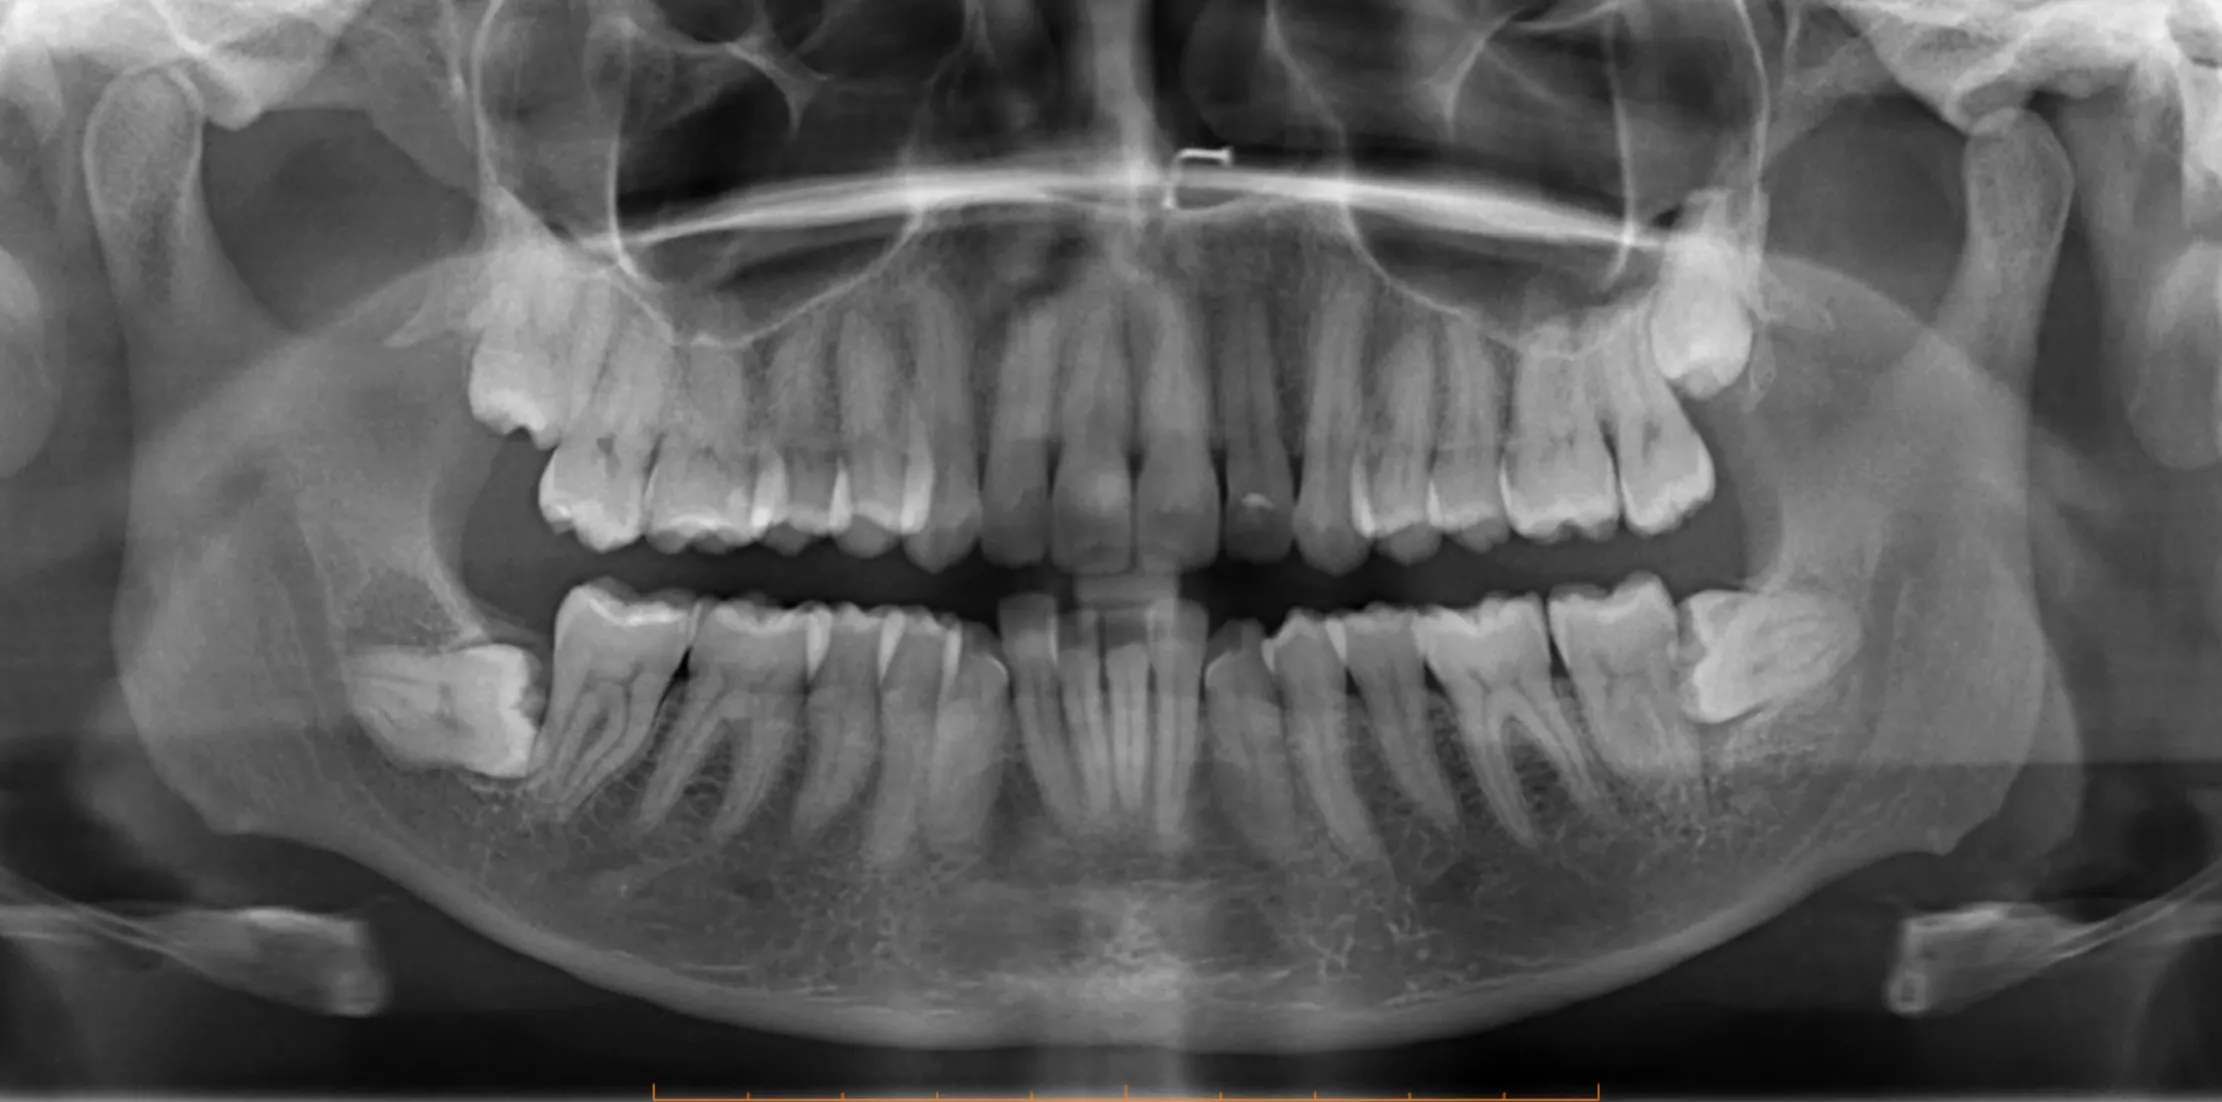

The Wisdom Teeth Removal Procedure

- Surgery: The surgical technique depends on the position and complexity of each tooth. For a straightforward erupted wisdom tooth, the extraction may simply involve elevating and removing the tooth.

- Impaction: For impacted teeth, a small incision is made in the gum, and in some cases, a small amount of bone around the tooth is removed to gain access. The tooth may be sectioned into pieces to make removal easier and minimise the amount of bone that needs removal.